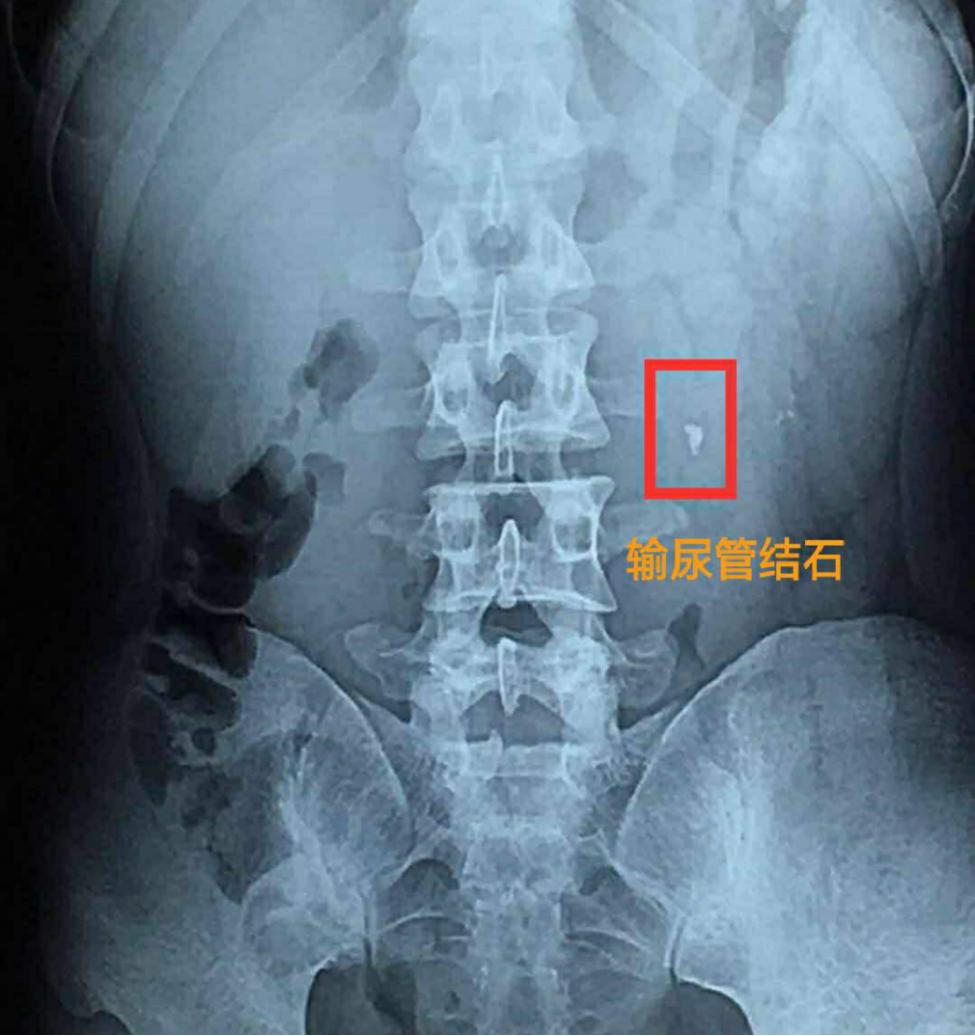

- 结石表面较圆滑,直径<0.6 cm:国内外泌尿科医师的多数意见认为,结石的直径是决定结石能否自行排出体外的重要因素,直径<0.6 cm的结石排出率超过90%;

- 结石未导致严重的梗阻积水,停留在局部位置的时间<2个星期;

- 结石以下的输尿管或尿道通畅,无狭窄或者梗阻;